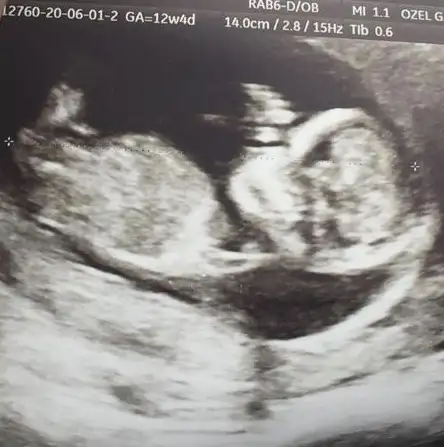

👫 11 yada 12 yada 13 hafta Nub usg nizi konumuza paylaşın

Arkadaşlar tahmin var mı? Özellikle ikra meyra :) Rabbim hayırlısını nasip etsin inşallah. 11+5